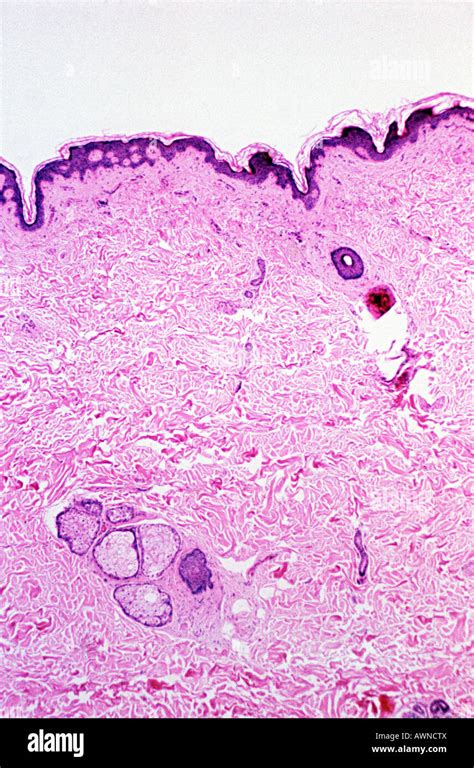

Microscopic View of Skin Cells

When we zoom in on the microscopic scale, we start to see the individual cells that make up the skin, each with its own distinct shape, size, and function. These include keratinocytes (which produce a protein called keratin that forms a protective barrier on the skin surface), melanocytes (which produce the pigment melanin that gives skin its color), Langerhans cells (which help our immune system recognize and respond to foreign invaders), and Merkel cells (which help us sense touch and pressure).

Closer Look at Epidermal Cells

One of the most beautiful and intricate structures in the epidermis is the stratum corneum, a layer of flattened, dead keratinocytes that form a complex mosaic pattern of intricate shapes and colors. When viewed under a microscope, these cells reveal an exquisite architecture of hexagons, pentagons, and triangles, reminiscent of a geometric tessellation or a stained-glass window in a Gothic cathedral.

The Fascinating Biology s of Dermis

Beneath the epidermis lies the dermis layer, which contains a vast network of blood vessels, lymphatics, nerve fibers, and extracellular matrix that give the skin its elasticity, resilience, and strength. Perhaps the most fascinating cells in the dermis are the fibroblasts, which are responsible for producing and maintaining the collagen and elastin fibers that give skin its structural integrity and flexibility. When viewed under a microscope, fibroblasts reveal a complex shape, with long, branching processes that extend out in all directions to interact with neighboring cells and tissues.